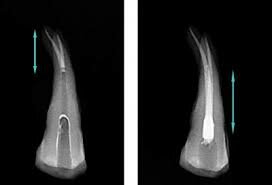

• LONGITUD RADICULAR Y NIVEL DE OBTURACIÓN

LONGITUD RADICULAR Y NIVEL DE OBTURACIÓN

Meyer L. Rhein, médico y dentista de Nueva York introdujo una técnica para determinar la longitud radicular y el nivel de la obturación.